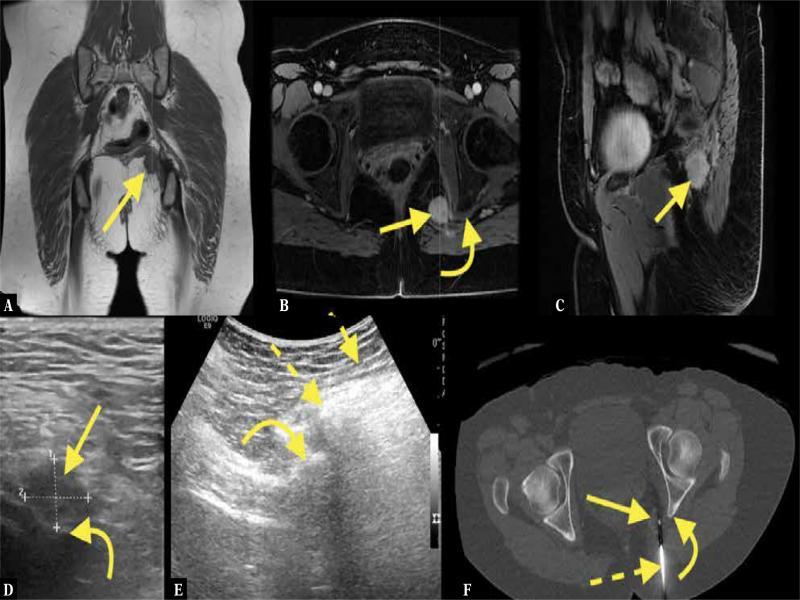

Fig. 9.

An 83-year-old patient with pain in the left buttock and leg. MRI of the pelvis with intravenous contrast revealed a tumor in the greater sciatic foramen ( A–C ; straight arrow – tumor, curved arrow – sciatic nerve). The MRI was unspecific; however, a diagnosis of malignant peripheral nerve sheath tumor was made because of the tumor’s direct relation to the sciatic nerve. The patient was referred for US-CNB ( D–F ; dashed arrows – biopsy needle). No histopathological diagnosis could be made. The patient was referred once again for US-CNB, where the histopathological diagnosis of benign peripheral nerve sheath tumor was made and confirmed after excisional biopsy